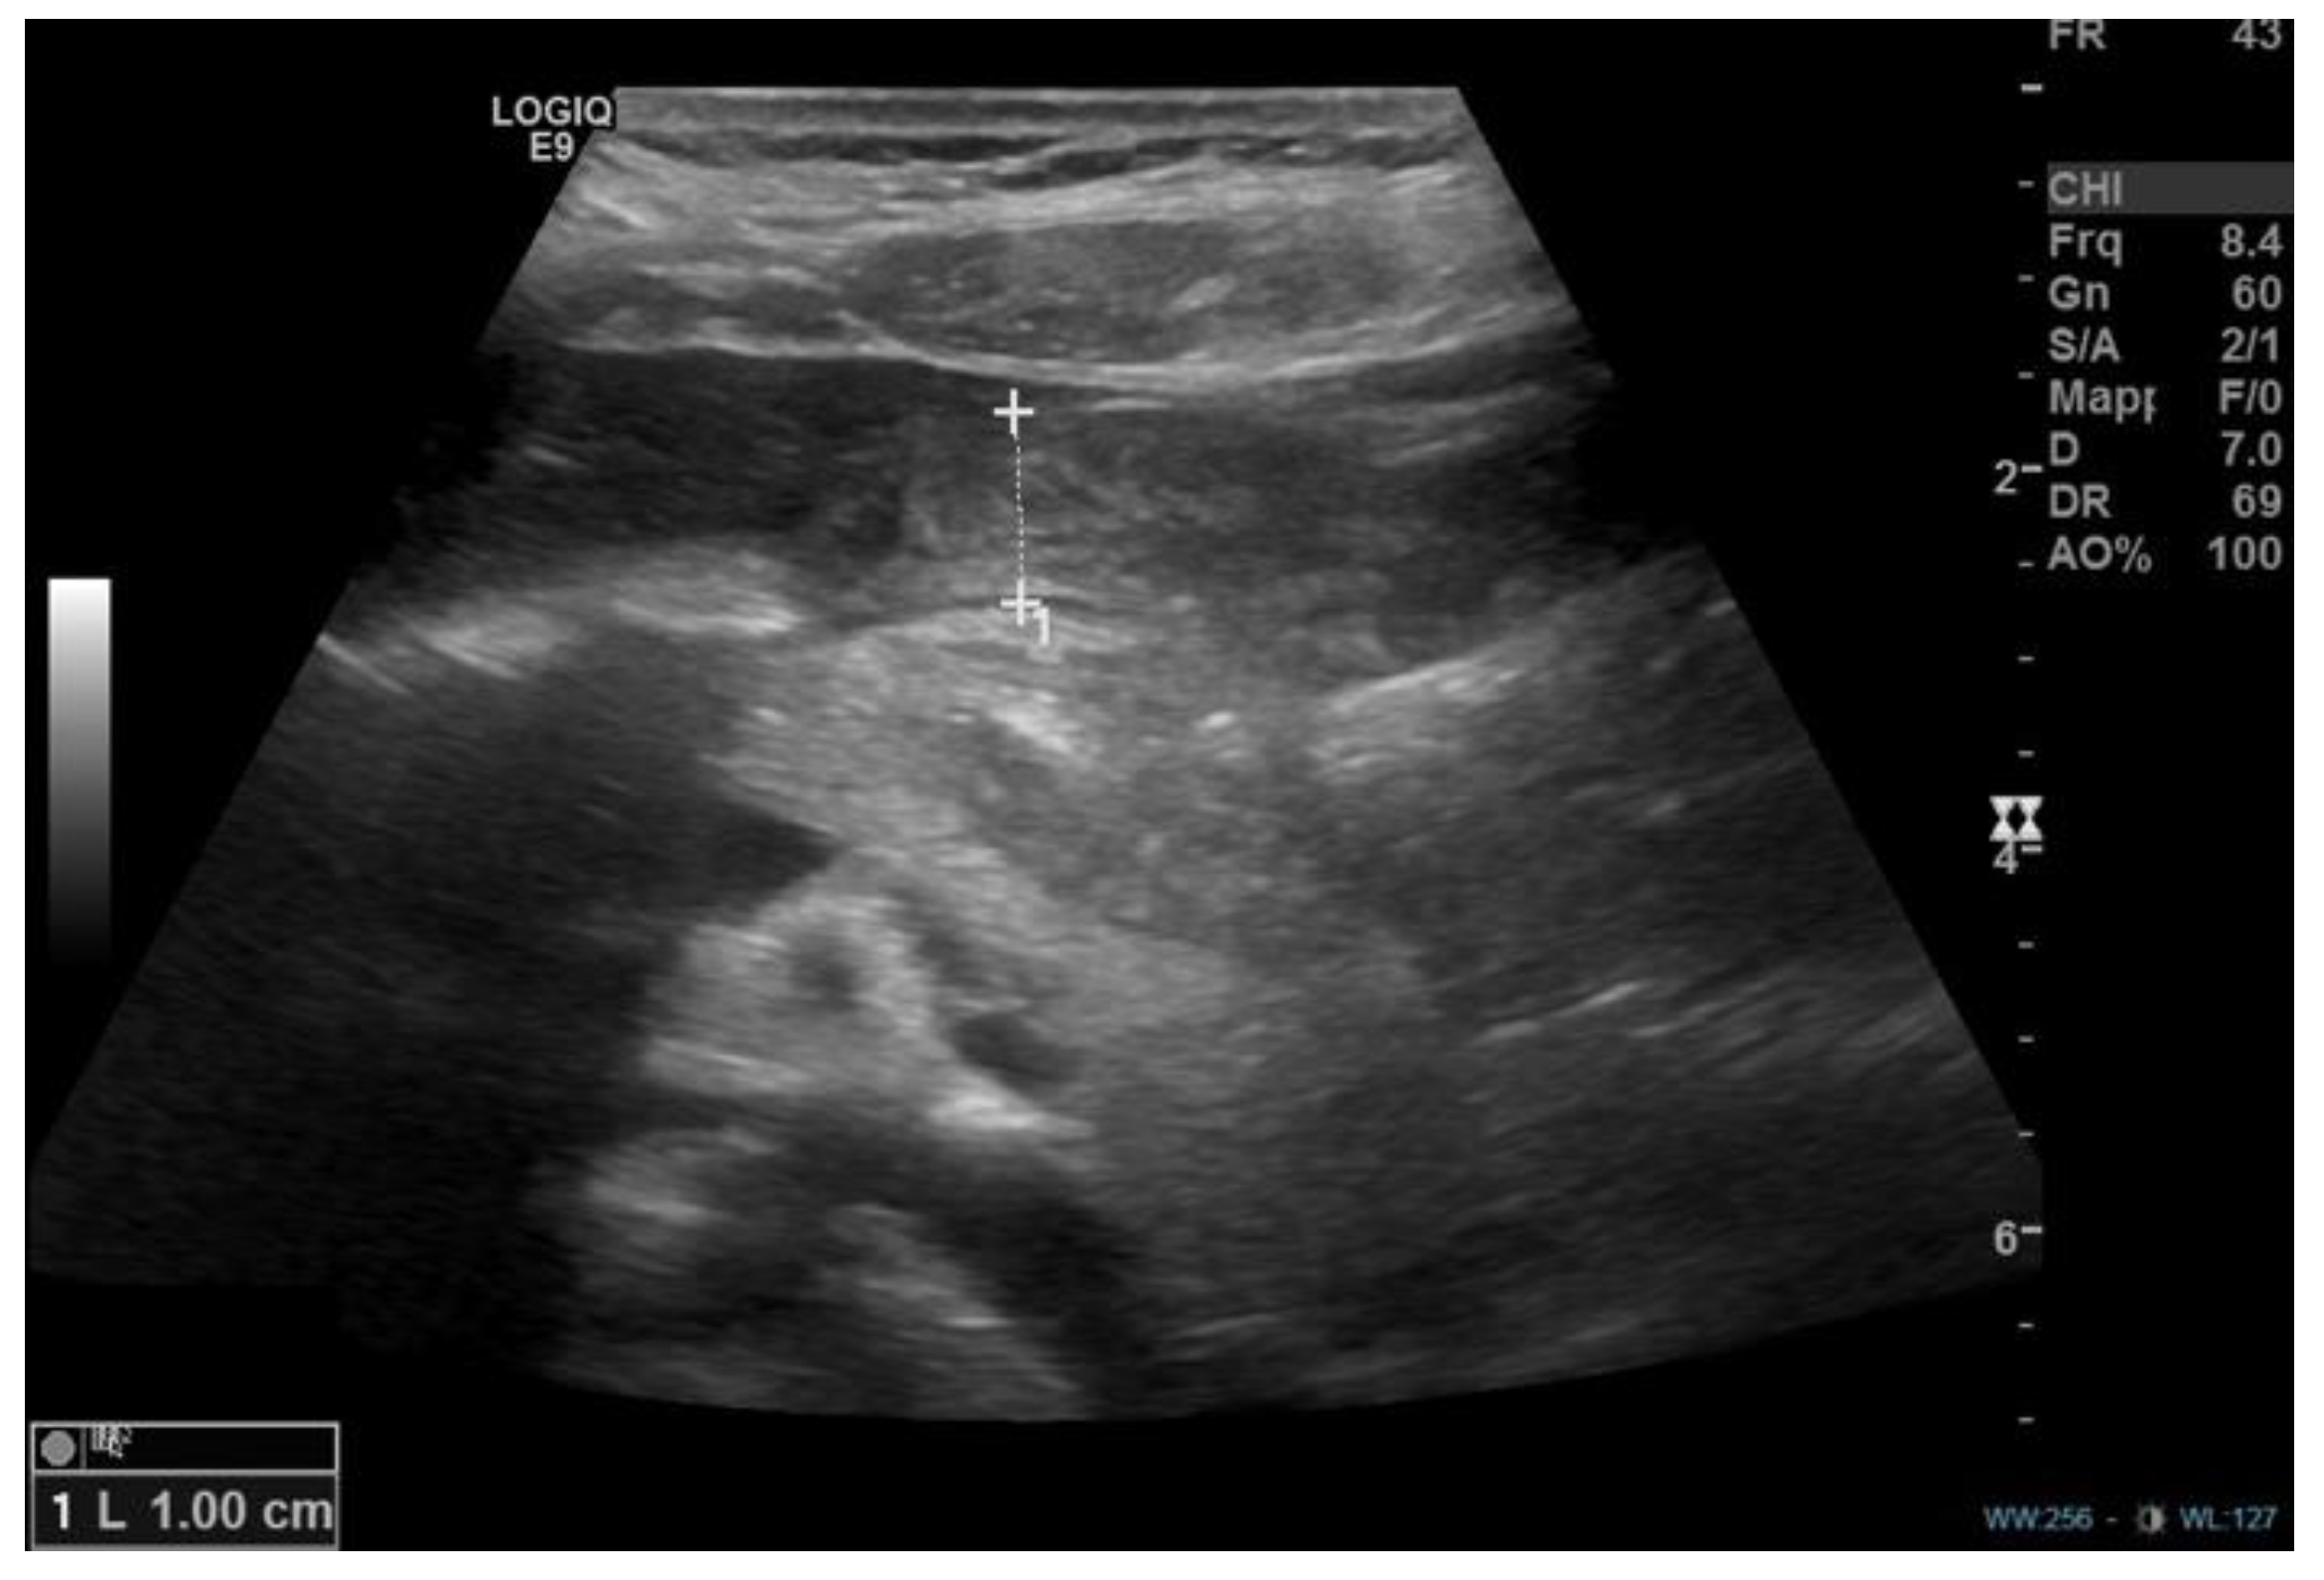

From www.wikidoc.org

Pyloric stenosis ultrasound wikidoc What Does Pyloric Stenosis Vomit Look Like pyloric stenosis is a thickening or swelling of the pylorus — the muscle between the stomach and the intestines — that causes. If someone is concerned a child may have pyloric stenosis, they should talk with a. ultrasound to view the pylorus and confirm a diagnosis of pyloric stenosis. projectile vomiting after a feeding is a hallmark. What Does Pyloric Stenosis Vomit Look Like.

Congenital Hypertrophic pyloric stenosis (CHPS) Creative Med Doses What Does Pyloric Stenosis Vomit Look Like ultrasound to view the pylorus and confirm a diagnosis of pyloric stenosis. pyloric stenosis diagnosis. what is pyloric stenosis? symptoms may include: The classic symptom is vomiting. However, with persistent vomiting the. If someone is concerned a child may have pyloric stenosis, they should talk with a. The vomiting often starts like a 'normal' vomit and. What Does Pyloric Stenosis Vomit Look Like.

Congenital Hypertrophic pyloric stenosis (CHPS) Creative Med Doses What Does Pyloric Stenosis Vomit Look Like It is more common in first born male infants. pyloric stenosis is a condition where the passage (pylorus) between the stomach and small bowel (duodenum) becomes. ultrasound to view the pylorus and confirm a diagnosis of pyloric stenosis. At first, your baby may only throw up once in a while. The vomiting often starts like a 'normal' vomit. What Does Pyloric Stenosis Vomit Look Like.

Pyloric Stenosis KidsHealth NZ What Does Pyloric Stenosis Vomit Look Like It affects babies from birth to 6 months of. As time goes by, your baby will throw up more often and in larger. Your pediatrician will ask questions about your baby's symptoms. As the pylorus valve thickens over time, the. the first symptom is usually vomiting. If your baby is vomiting forcefully, call his doctor right away. ultrasound. What Does Pyloric Stenosis Vomit Look Like.